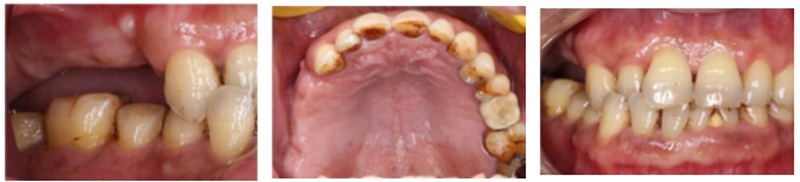

檢查:患者14、15、16、17缺失,無紅腫潰瘍,牙齦情況良好,口腔衛(wèi)生狀況良好。

診斷:14、15、16、17缺失

處理:通過數(shù)字化種植導航進行15、16、17種植修復

術前準備

®石膏模型上進行排牙確定患者咬合關系,取放射阻射材料灌于缺牙區(qū),患者戴著處理過的

配準裝置拍攝術前CBCT。

®根據(jù)CBCT中牙冠顯影位置,按照修復引導種植的原則進行方案設計

修復完成